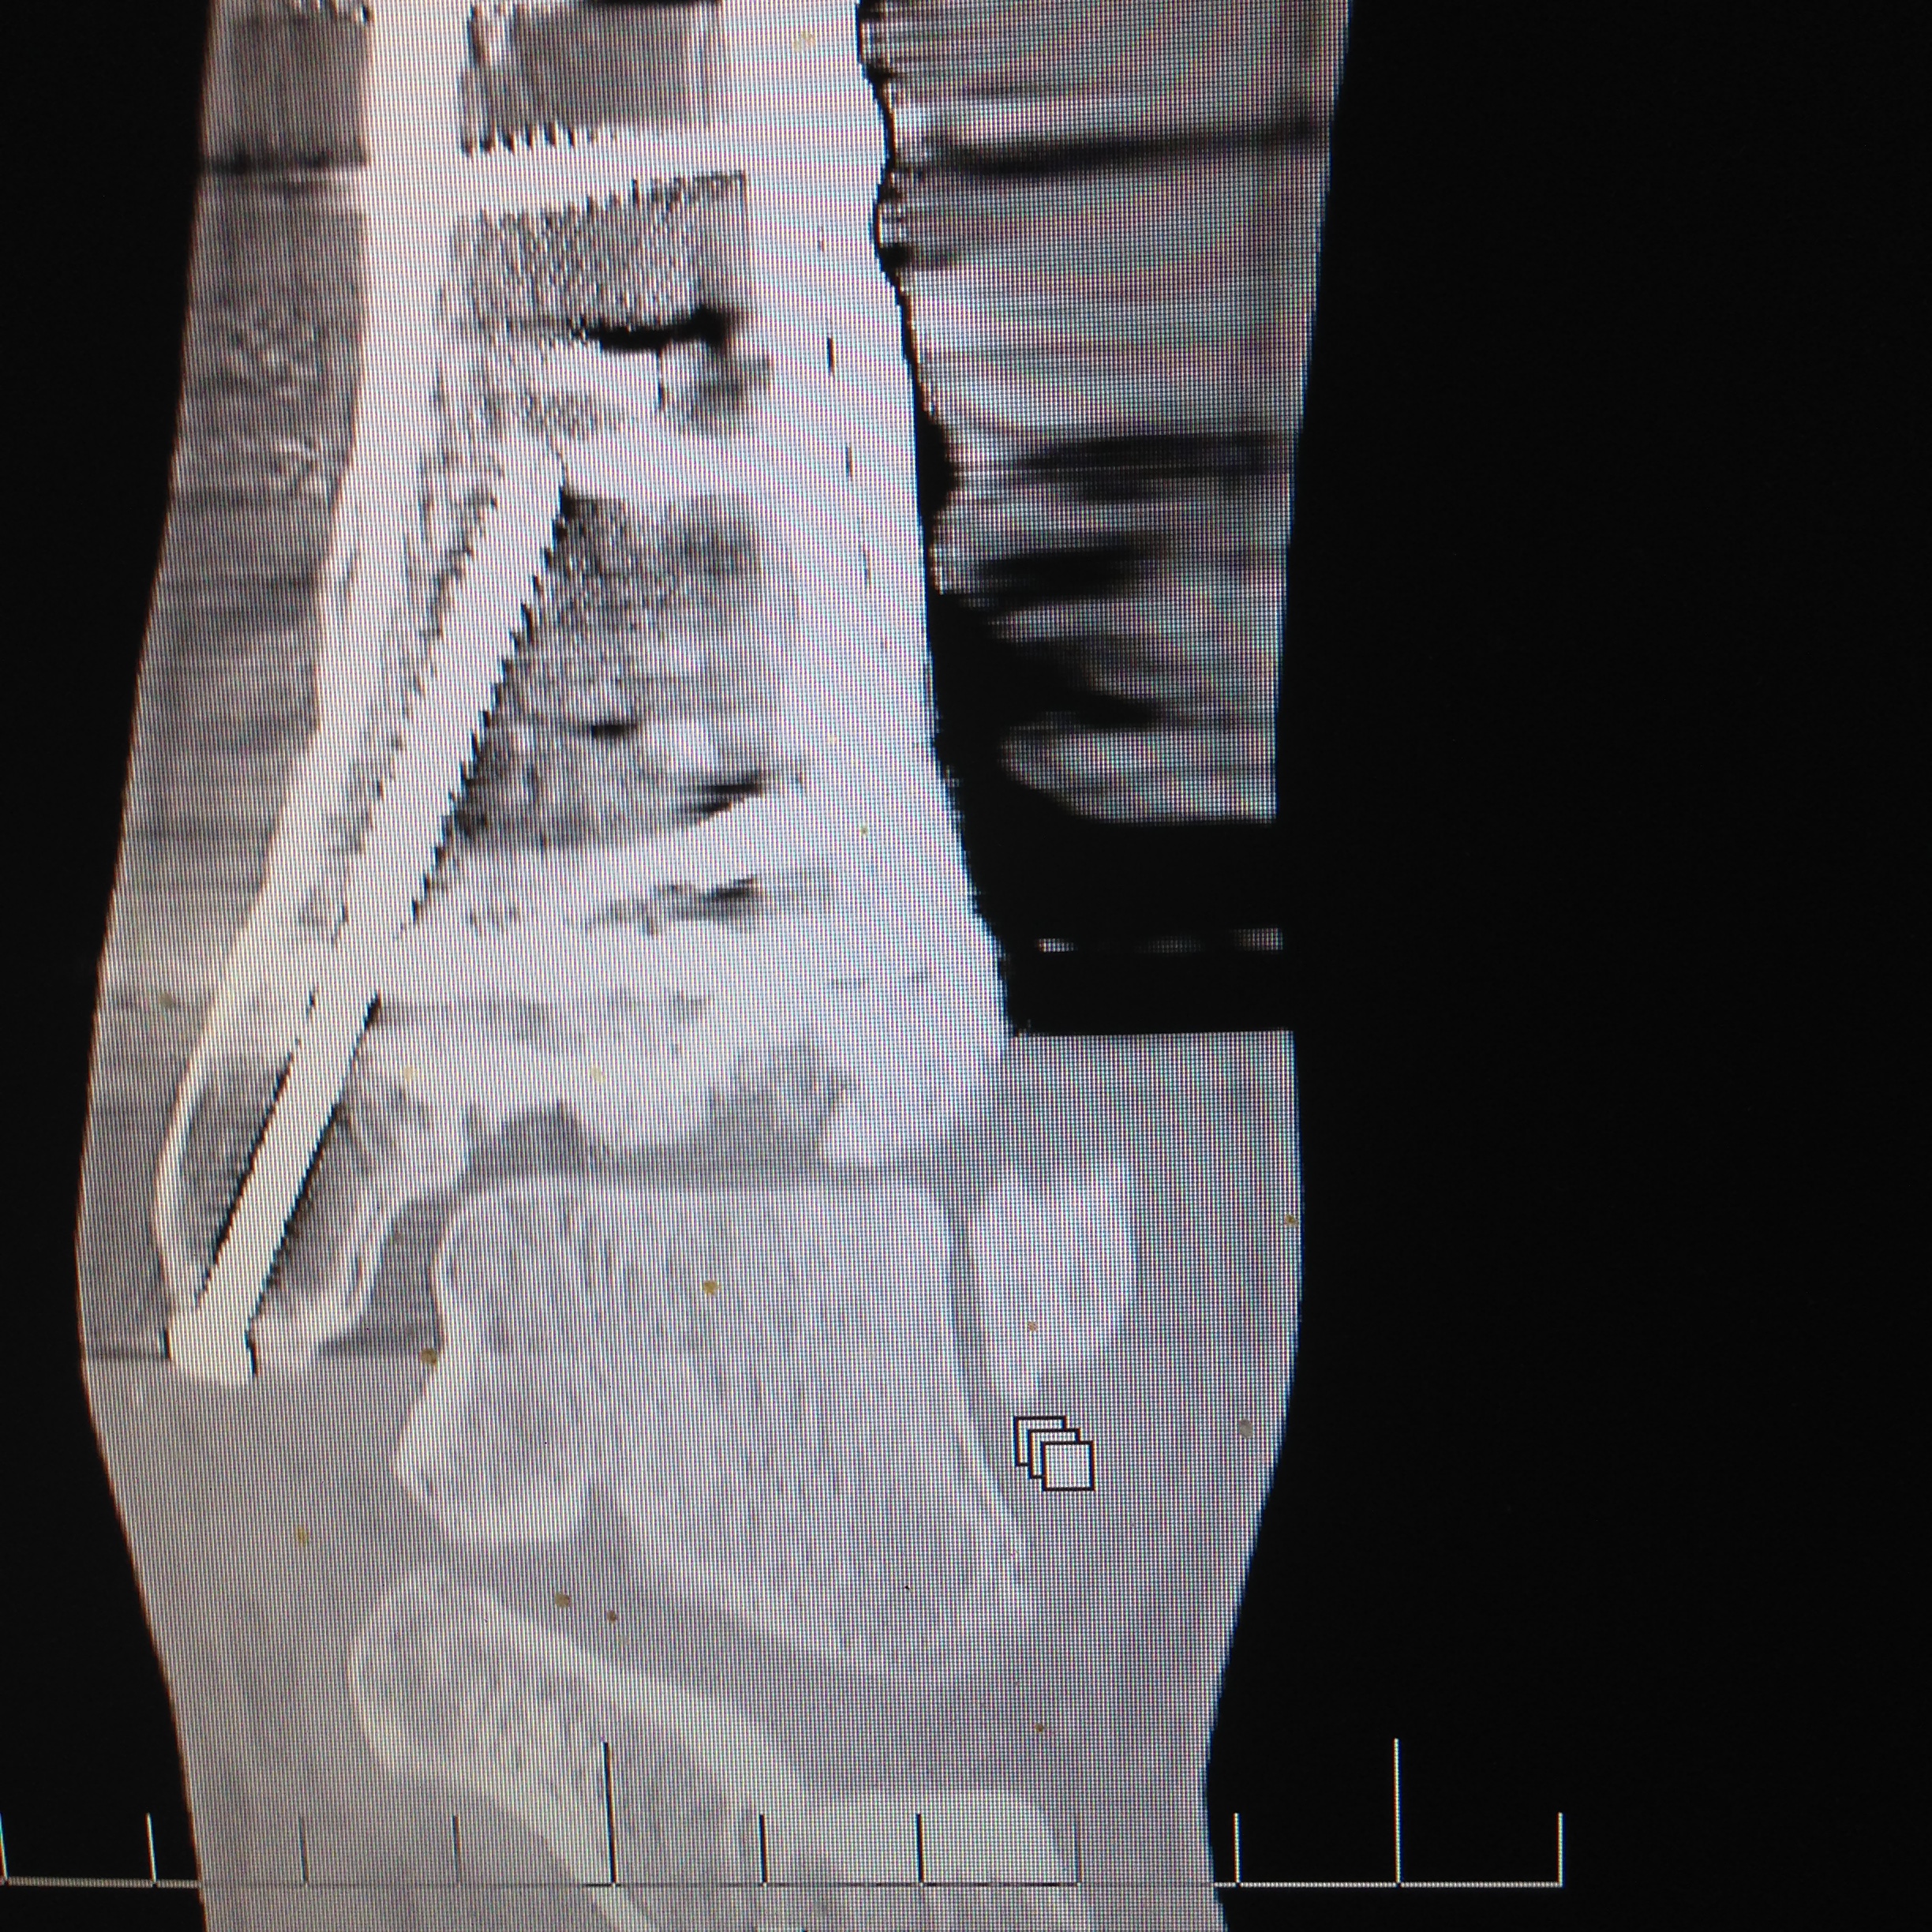

2015-12-03 09.16.29 Published December 6, 2015 at 2448 × 2448 in Ankle replacement not an option, Fusion needs to wait too